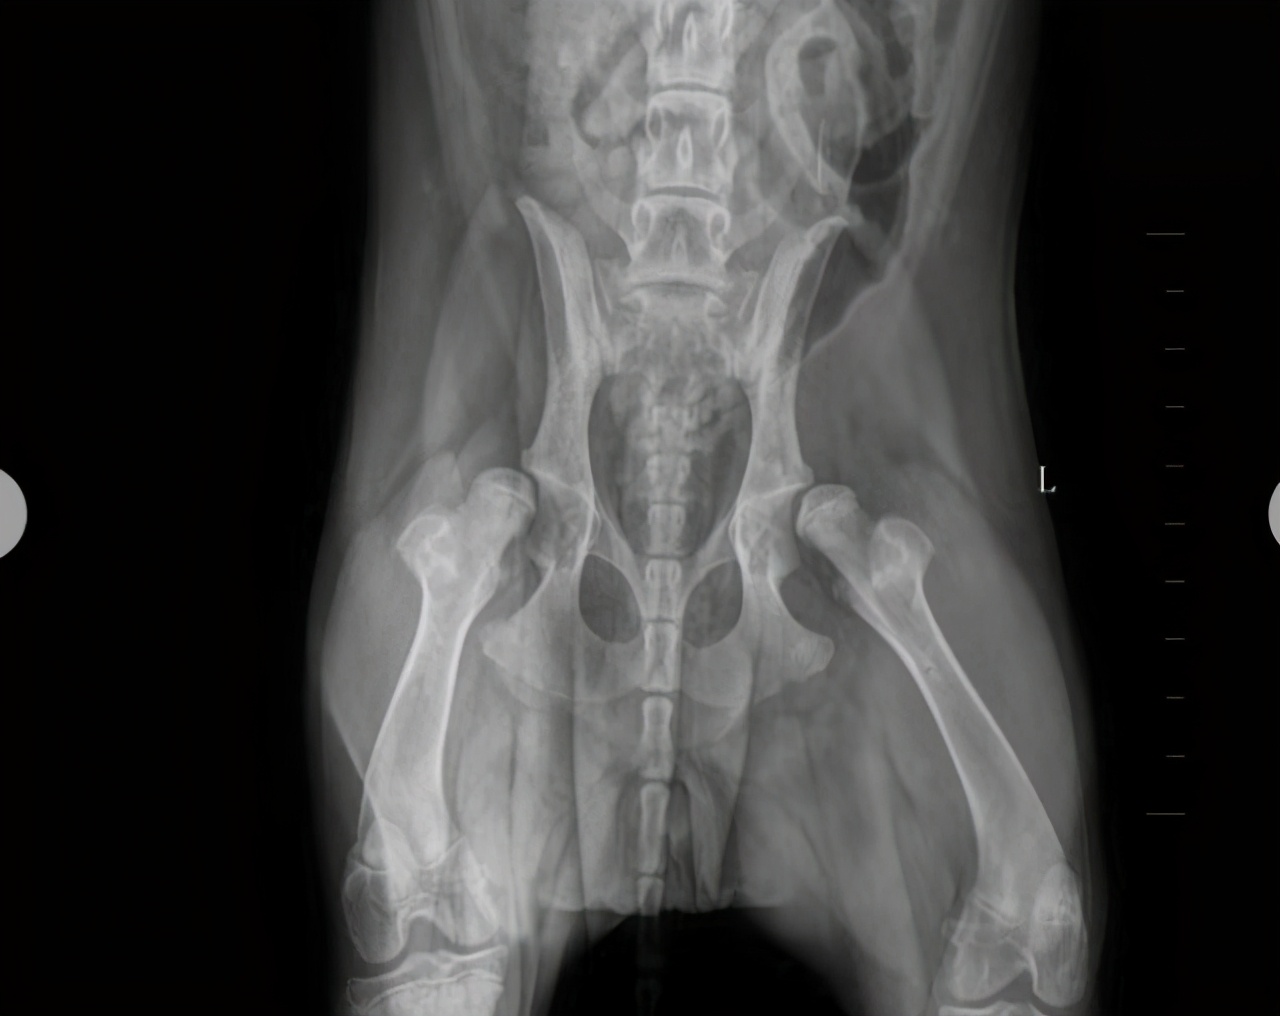

三、别让它经常爬楼梯

金毛犬属于中大型犬,它们容易出现髋关节发育不良的情况。所以铲屎官要注意好,不要让金毛犬经常爬楼梯哦,还有,尽量不要让它从高处跳下,不然容易伤害它们的关节。

主人也要重视金毛犬从小的补钙工作,有助于增强它们的骨骼哦。